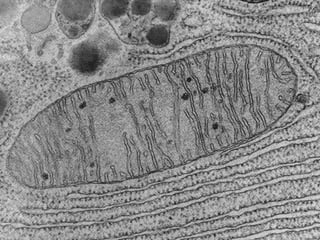

Este documento presenta imágenes microscópicas de diferentes tipos de tejidos y estructuras celulares teñidas con varios métodos histológicos. Incluye fotografías que muestran fibras de colágeno, elásticas y reticulares en diversos órganos, así como membranas basales y células especializadas de órganos como riñones, glándulas mamarias y próstata. El propósito es demostrar la aplicación de técnicas histológicas para visualizar componentes celulares y tej